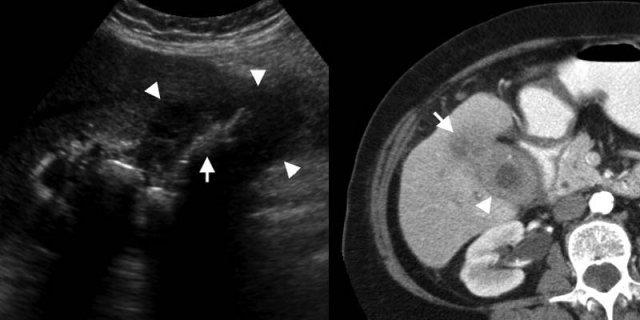

Nam giới 56 tuổi bị xơ gan. TRÁI: Siêu âm cho thấy dày thành túi mật (mũi tên), xung quanh có dịch cổ trướng. Lưu ý nhu mô gan xơ không đều. PHẢI: Trên CT có thuốc cản quang, thành túi mật (mũi tên) trông gần như bình thường, do phù nề dưới thanh mạc không thể phân biệt rõ với dịch cổ trướng xung quanh trên CT.

Xơ gan

Các bệnh lý toàn thân như rối loạn chức năng gan, suy tim hoặc suy thận có thể dẫn đến dày thành túi mật lan tỏa [1, 2].

Cơ chế bệnh sinh chính xác gây ra phù nề thành túi mật trong các bệnh cảnh đa dạng này vẫn chưa được xác định rõ, nhưng nhiều khả năng là do tăng áp lực tĩnh mạch cửa, tăng áp lực tĩnh mạch hệ thống, giảm áp lực thẩm thấu nội mạch, hoặc sự kết hợp của các yếu tố này.

Xơ gan, viêm gan và suy tim phải sung huyết là những nguyên nhân tương đối thường gặp.

Trường hợp bên trái là bệnh nhân bị xơ gan.

Dày thành túi mật thứ phát có thể là do tăng áp lực tĩnh mạch cửa và giảm áp lực thẩm thấu nội mạch.